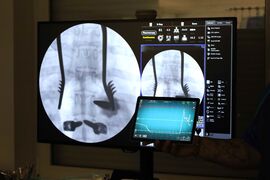

Nový systém funguje jednoducho. K zvukovému signálu, ktorý lekári pri zavádzaní skrutky počujú, pridáva aj vizuálne zobrazenie v počítači. Vďaka tomu je orientácia počas zákroku ešte presnejšia a prehľadnejšia. Zároveň umožňuje údaje zaznamenávať a uchovávať ako dôkaz správneho umiestnenia skrutky. „Pri operáciách detských pacientov so skoliózou, najmä pri operáciách idiopatických skolióz, sa do chrbtice zavádza väčší počet skrutiek, pričom každý stavec si vyžaduje individuálne a presné nasmerovanie. Skrutky sa pritom zavádzajú v blízkosti miechy, čo kladie vysoké nároky na presnosť zákroku. Každý stavec je pri deformite otočený inak, a preto je presnosť kľúčová. Skrutky zavádzame v blízkosti miechy, kde nie je priestor na chybu. Aj vďaka tejto technológii môžeme robiť zákroky ešte bezpečnejšie,“ uzavrel Juraj Popluhár s tým, že neoceniteľnou výhodou je aj to, že získané údaje môžu využiť pri ďalšom zlepšovaní postupov či pri vzdelávaní mladých operatérov.